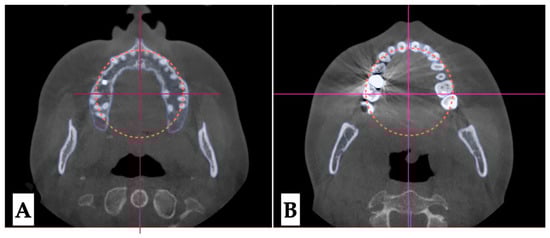

2.3.2. Design of 3D Surgical Guide

2.3.3. Osteotomy Planning and Appliance Design

2.3.4. Postoperative Assessment, Outcome Analysis, and Asymmetry Correction